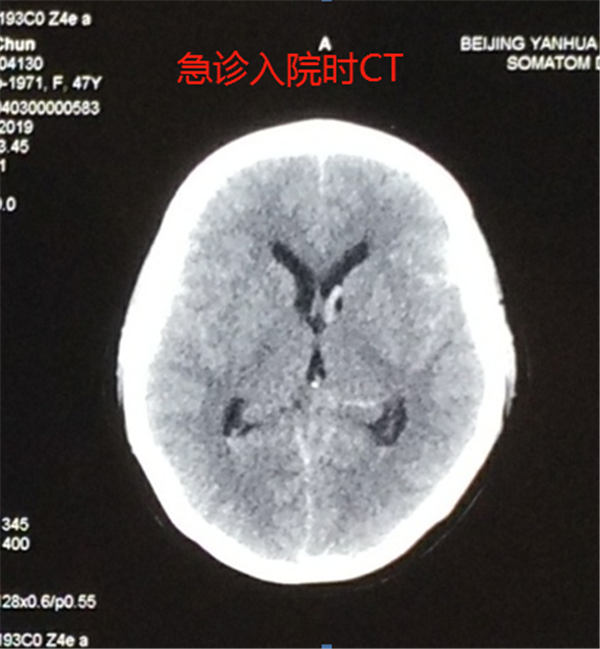

燕化医院神经外科经头颅CT检查发现,患者蛛网膜下腔出血,考虑脑动脉瘤破裂引起出血,遂给予止血等对症治疗,考虑病情较重,便紧急安排入院,以寻求进一步的治疗。

后经进一步的检查分析,医生在她的头颅CT平扫片子上发现了症结所在——在右侧颈内动脉及颈椎动脉均有可疑动脉瘤。